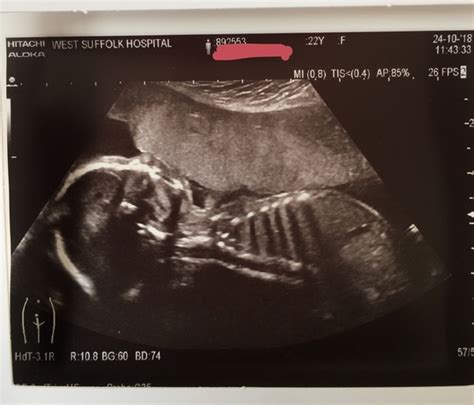

Alright guys, let’s get down to brass tacks about this all-important 20-week scan. It’s officially called the anomaly scan, and its primary goal isn’t just to figure out if you’re having a boy or a girl (though that’s a fun bonus!). The real reason for this detailed ultrasound is to check your baby from head to toe for any major physical abnormalities or anomalies . Think of it as a really thorough check-up for your developing little human. Sonographers are trained to meticulously examine everything: the baby’s brain, face (including lips and palate), spine, heart (looking at the four chambers and major blood vessels), chest, abdomen, kidneys, bladder, and all four limbs. They’re also checking the placenta and the umbilical cord to make sure everything is functioning as it should be. The length of your baby and the amount of amniotic fluid are also measured. It’s a pretty comprehensive picture, and that’s why it can take a while – sometimes up to an hour! The technicians are basically looking for any deviations from the typical development. This can include things like cleft lip, spina bifida, certain heart defects, or issues with organ development. It’s important to remember that this scan detects major structural problems. It won’t pick up every single condition, especially genetic syndromes or more subtle issues. The medical professionals performing the scan are highly skilled, but it’s still a visual assessment, and there are limitations. The scans are usually performed abdominally, but if the baby’s position isn’t ideal or the view is obstructed by the mother’s body, a transvaginal scan might be offered, though this is less common at 20 weeks. The detailed nature of the scan is precisely why any unexpected findings can be so concerning, leading many mums to seek out shared experiences and advice on platforms like Mumsnet.